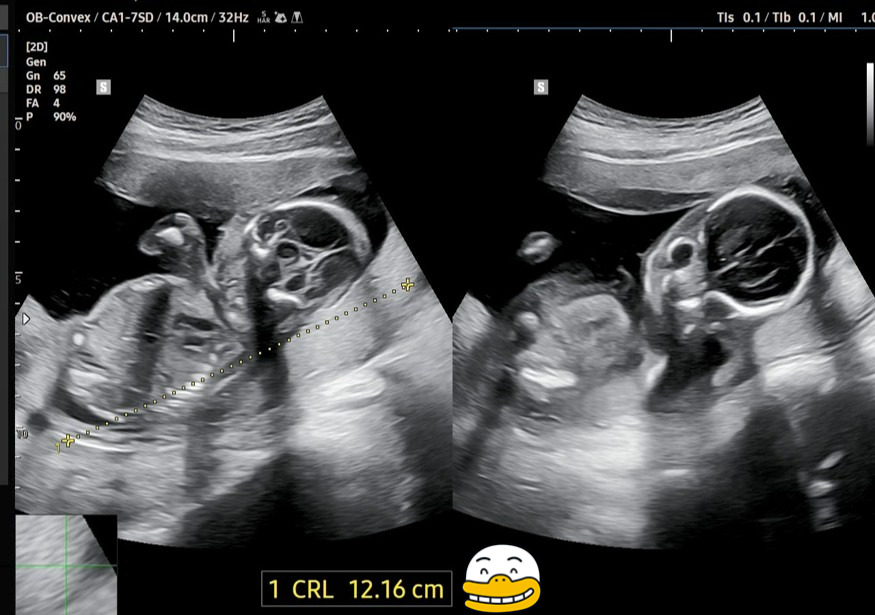

이번에 새롭게 딸애가 보내준 초음파 사진을 다시 확인해 보았습니다.

태아의 심장박동수는 155 bpm이고, 태아 머리부터 엉덩이까지의 길이(CRL)는 12.16㎝라고 나오네요.

딸애가 그러는데 담당의사가 '팡팡이'의 CRL은 평균보다 조금 작고, BPD(머리 옆통수의 길이)는 평균보다 조금 크다고 했다고 하네요. 초음파로 측정한 값이니 다소 오차가 있을 것이라는 생각은 듭니다.

그런데 초음파 영상을 보는데 GA(Gestational Age, 임신 주수)가 17w6d±10d라고 나오고, EDD(Expected Date of Delivery, 분만 예정일)도 2025.7.8일이라고 나오네요.

지난번 16주 차 초음파에서는 임신 주수가 16w1d±8d, 분만 예정일이 2025.6.30이었는데, 대략 1주일 정도가 뒤로 늦춰진 것 같네요.